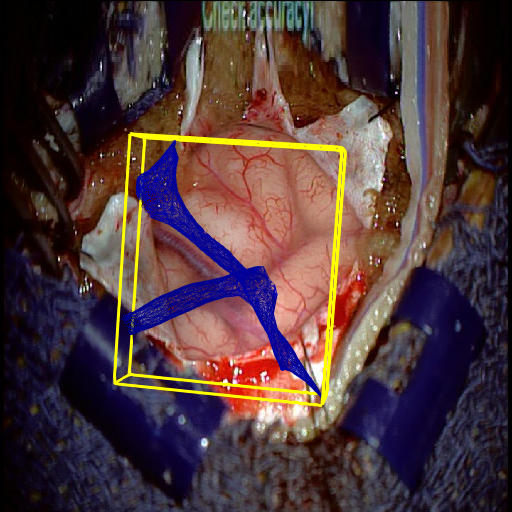

We tested our method retrospectively on 6 clinical datasets from 6 patients (cases) (see Fig. 5). These consisted of preoperative T1 contrast MRI scans and intraoperative images of the brain surface after dura opening. Cortical vessels around the tumors were segmented and triangulated to generate 3D meshes using 3D Slicer. We generated 100 poses for each 3D mesh (i.e.: each case) and used a total of 15 unique textures from human brain surfaces (different from our 6 clinical datasets) for synthesis using . In order to account for potential intraoperative brain deformations [4] we augment the textured projection with elastic deformation [21] resulting in approximately 1500 images per case. The surgical images of the brain (left image of the stereoscopic camera) were acquired with a Carl Zeiss surgical microscope. The ground-truth poses were obtained by manually aligning the 3D meshes on their corresponding images.

Test and Comparison on Clinical Images

We compared our method (Ours) with segmentation-based methods (ProbSEG) and (BinSEG) [7]. These methods use learning-based models to extract binary images and probability maps of cortical vessels to drive the registration. We report in Tab. 1 the distances between the ground truth and estimated poses. Our method outperformed ProbSEG and BinSEG with an average ADD error of mm compared to mm and mm, respectively. Our errors remain below clinically measured neuronavigation errors reported in [4], in which a mm average initial registration error was measured in 15 craniotomy cases using intraoperative ultrasound. Our method outperformed ProbSEG in 5 cases out of 6 and BinSEG in all cases and remained within the clinically measured errors without the need to segment cortical vessels or select landmarks from the intraoperative image. Our method also showed fast intraoperative computation times. It required an average of only milliseconds to predict the pose (tested on research code on a laptop with NVidia GeForce GTX 1070 8GB without any specific optimization), suggesting a potential use for real-time temporal tracking.

Fig. 5 shows our results as Augmented Reality views with bounding boxes and overlaid meshes. Our method produced visually consistent alignments for all 6 clinical cases without the need for initial registration. Because our current method does not account for brain-shift deformation, our method produced some misalignment errors. However, in all cases, our predictions are similar to the ground truth.